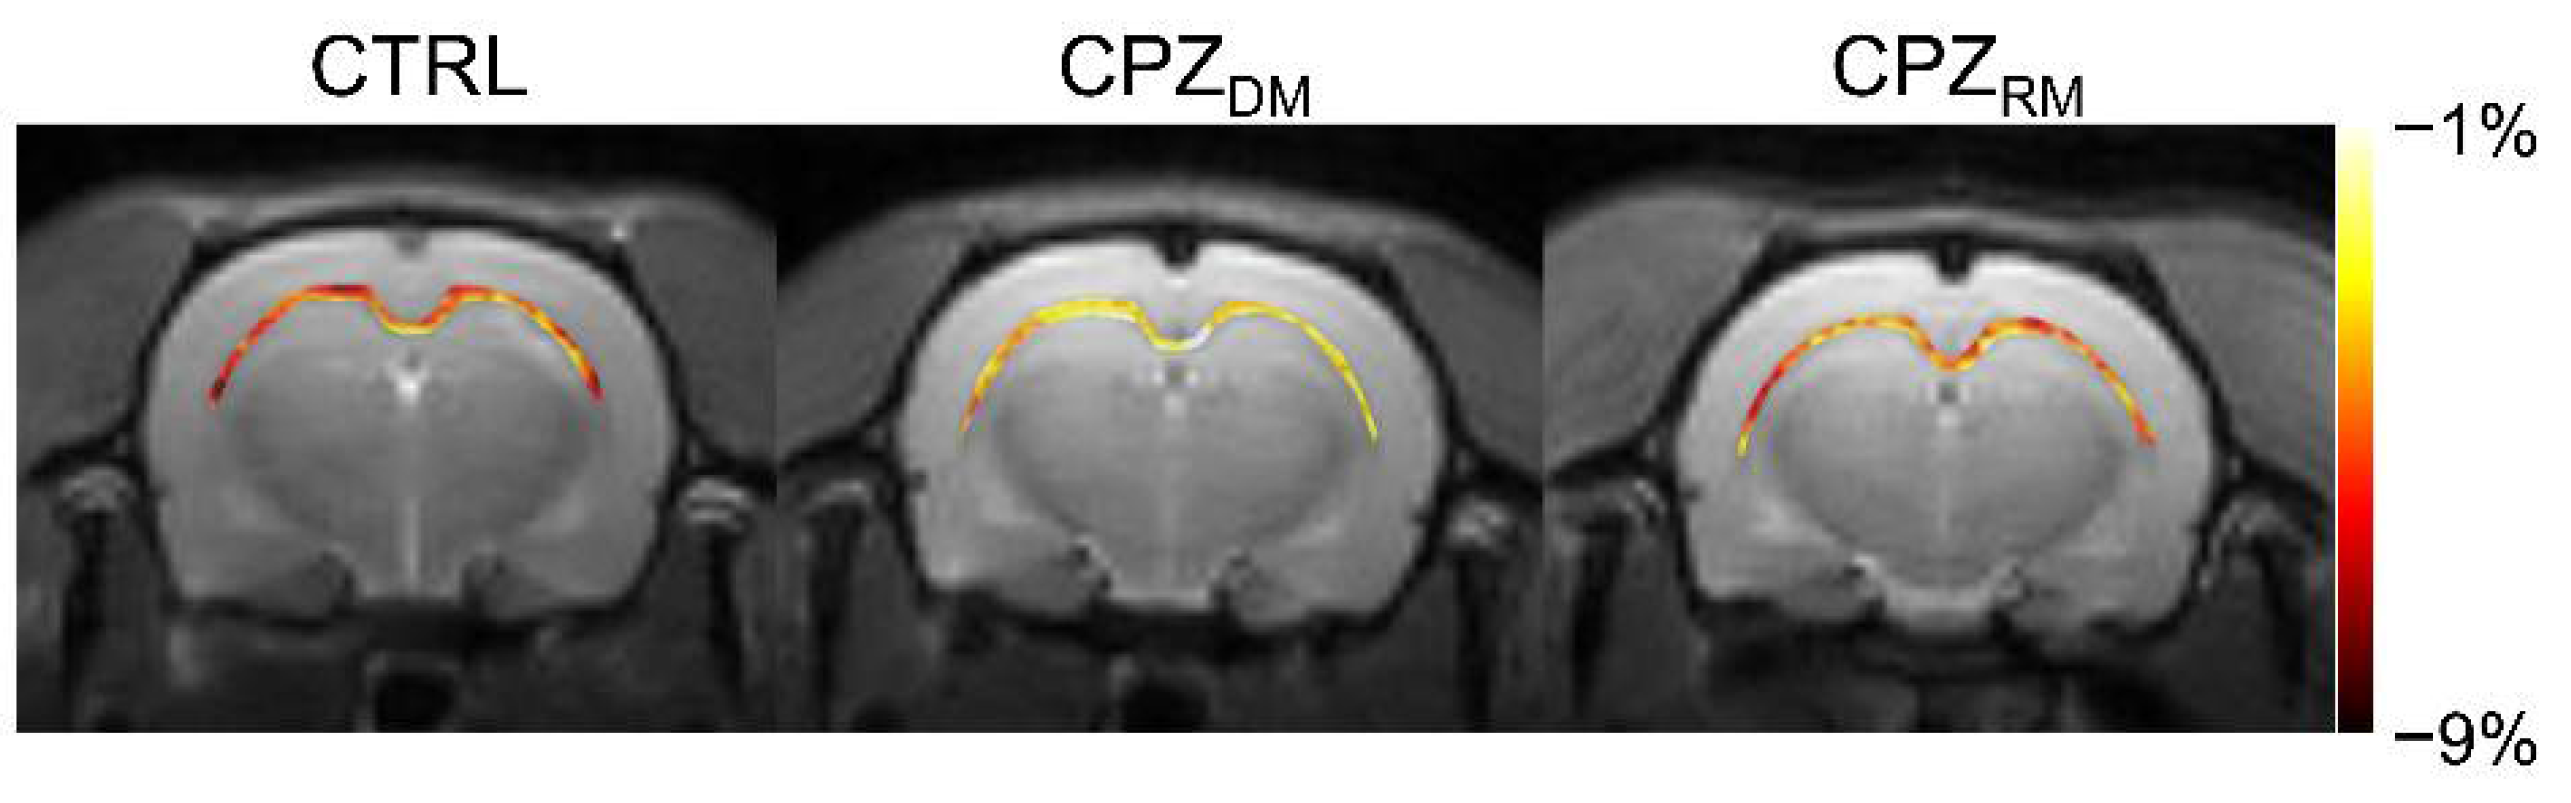

Figure 2 shows the mapping results of GluCEST signals in representative rats, with a focus on the CC region and overlaid on the unsaturated CEST image in each group. The GluCEST signals in the CC region changed hyperintensities as demyelination progressed, compared to the normal control. Moreover, the GluCEST image contrast decreased again in the CPZRM group compared to that in the CPZDM group, which did not differ significantly from that in the CTRL group, as shown in Figure 1b.

Figure 2.

Reconstructed glutamate-weighted chemical exchange saturation transfer (GluCEST) maps overlaid on the unsaturated image targeting the corpus callosum region from representative rats from the normal control (CTRL), demyelination (CPZDM), and remyelination (CPZRM) groups.